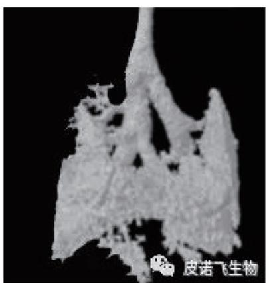

肺部组织 胚胎组织

小动物活体 CT 扫描